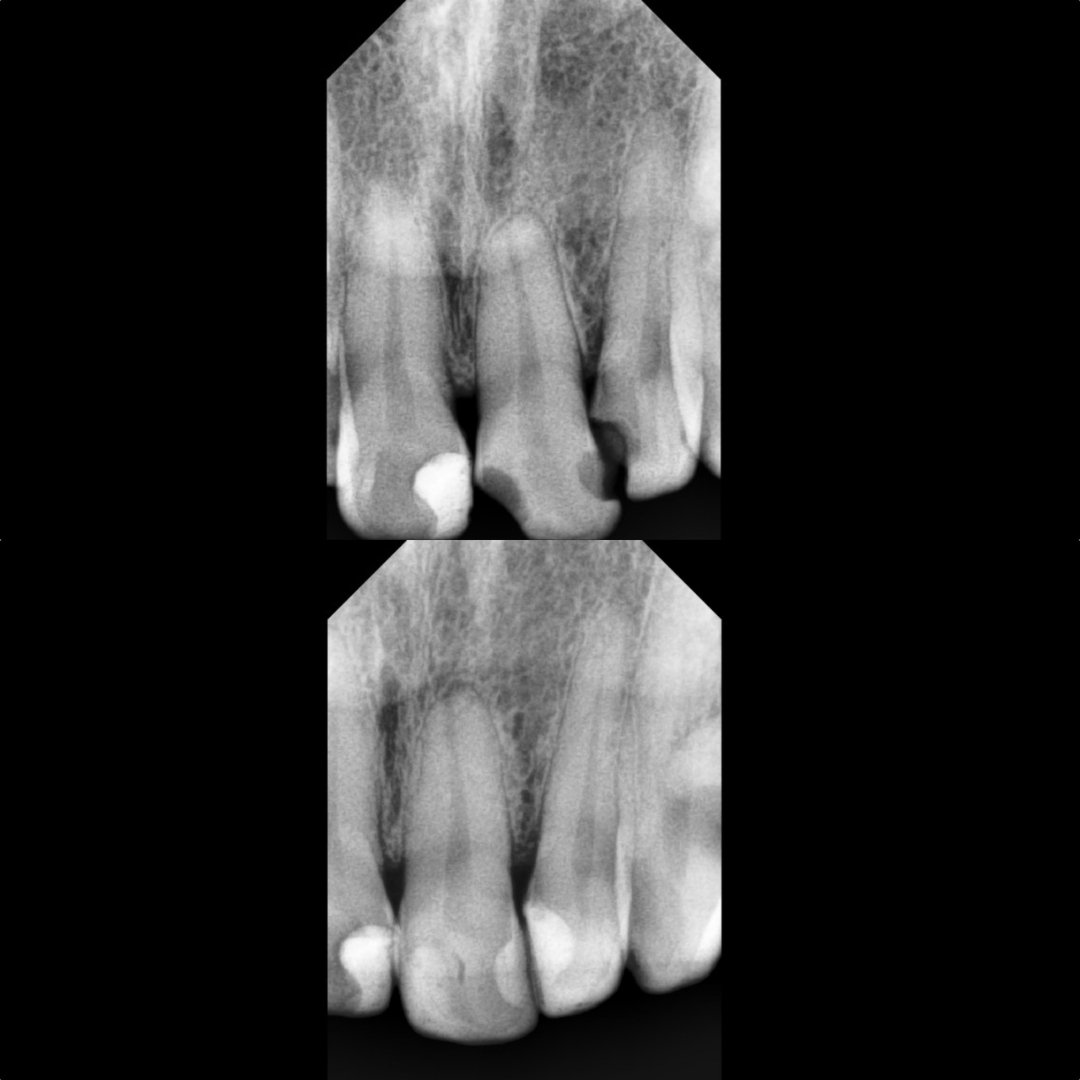

Before After Perawatan Saluran Akar (PSA) di Klinik Utama Pondok Gigi Jakarta

Transformasi nyata setelah perawatan saluran akar (PSA) di Klinik Utama Pondok Gigi Jakarta. Dari gigi rusak dan nyeri hingga kembali sehat dan berfungsi normal. Dikerjakan oleh dokter gigi profesional dengan teknik endodontik modern dan alat berteknologi tinggi untuk hasil maksimal.